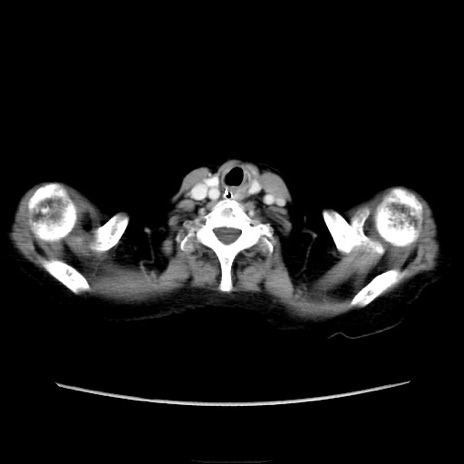

症例40(横断像)

【症例】90歳代女性

【主訴】腹痛・嘔吐

【現病歴】 食欲低下、嘔吐があり昨日他院受診。肺炎と診断され入院となる。入院後より腹部全体に圧痛あり。胃管留置され経過みていたが、症状持続するため、

当院転院となる。

【既往歴】胸椎圧迫骨折、胆石症

【身体所見】腹部:中央に激痛あり、圧痛あり、反跳痛不明

【データ】WBC 17100、CRP 18.82

横断像